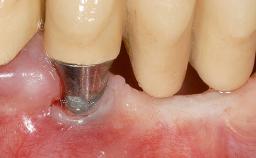

| # of Teeth | 1 |

| # of Implants | 1 |

| Attachment | One-Piece |

| Soft Tissue Grafting | Simultaneous |

| Abutment Type | Standard |

| Prosthesis Type | FDP |